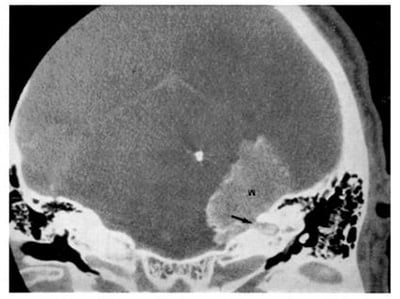

Hình 1.71. U màng não vôi hóa. Lát cắt mỏng ngang qua khối u nằm ở góc cầu tiểu não bên phải.